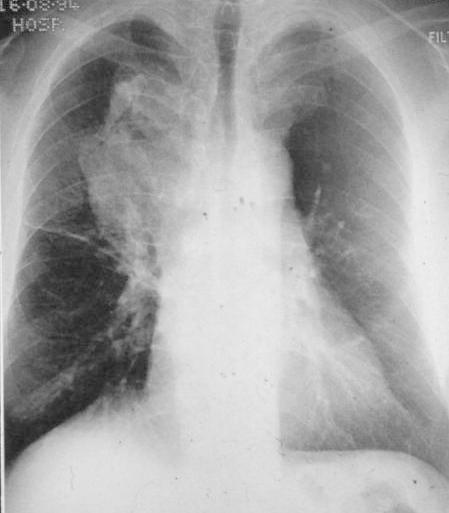

INSPIRATION

Poor Inspiration (picture to the right -->):

* False enlarged heart

* Difficult evaluation of the lungs

Same patient on inspiration (below):